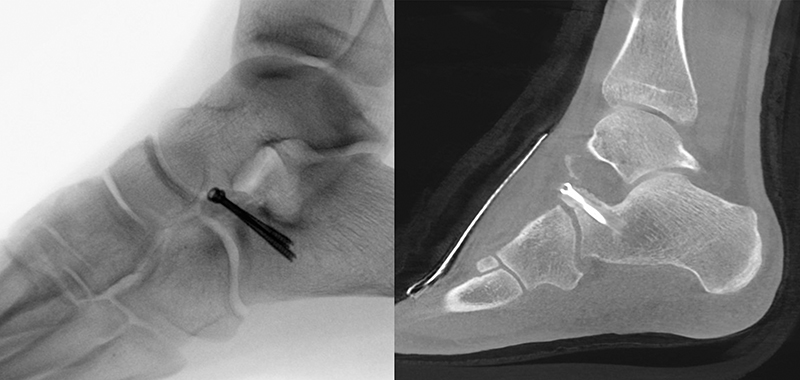

Bei Distorsionen des Sprunggelenks/Fußes stellen konventionelle Röntgenaufnahmen die initiale Standarddiagnostik dar 2021. In Abhängigkeit der Beschwerdelokalisation sollten Röntgenaufnahmen des Sprunggelenks in zwei Ebenen bzw. des Fußes in drei Ebenen angefertigt werden. Frakturen des Processus anterior werden aufgrund von Überlagerungen oder aufgrund von Fehlinterpretation als akzessorischer Knochen (Calcaneus secundarium) nativradiologisch häufig übersehen 3201. Ein zuverlässiger Frakturausschluss sowie die Erfassung von Begleitverletzungen ist nur mittels Schnittbildgebung möglich 22022. Aufgrund der breiten und schnellen Verfügbarkeit ist die Computertomographie (CT) das Verfahren der Wahl 2022. Bei Vorliegen eines plantaren Hämatoms, Hinweisen auf Verletzungen der Chopart-Gelenk-Linie (z. B. talonavikulare Kapselband-Avulsion) oder einer Diskrepanz zwischen der klinischen Untersuchung und der Röntgen-Bildgebung sollte eine CT-Diagnostik veranlasst werden 920197. In der Primärdiagnostik spielt die Magnetresonanztomographie (MRT) eher eine untergeordnete Rolle, da das fokale Knochenödem und das umgebende Weichteilhämatom dazu führen, dass kleinere knöcherne Avulsionen und/oder Bandverletzungen nicht klar differenziert werden können 20.

Begleitverletzungen

Häufig kommt es im Rahmen von PAC Frakturen zu knöchernen und/oder ligamentären Begleitverletzungen 20227. Eine aktuelle MRT-Studie wies in mehr als 2/3 der untersuchten Fälle Begleitverletzungen innerhalb des TN-Gelenks und in allen Fällen Verletzungen innerhalb des CC-Gelenks nach (z. B. talo-naviculare Avulsionen, Frakturen des Os cuboideum/Os naviculare, Rupturen/Avulsionsfrakturen des Lig. bifurkatum/Lig. calcaneo-cuboideum dorsale) 207. In Abbildung 1 und 2 sind häufig beobachtete Begleitverletzungen exemplarisch dargestellt.

Zum Lesen der Bildbeschreibung und zur Vollansicht bitte die Bilder anklicken. Bilder: M. Walther